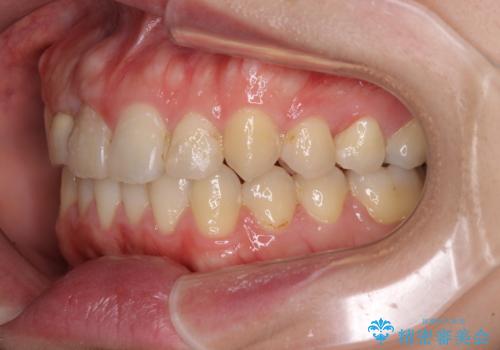

- 上下のデコボコと奥歯の咬みにくさを気にして来院された患者様です。

上顎骨の幅が下顎骨よりも小さいので、拡大装置により骨幅を広げて上下関係を改善し、その後インビザラインにて歯並びを整えることとしました。

上下の骨幅を改善したことで、スムーズに歯列矯正を行うことができました。

奥歯の咬み合わせを改善する必要があったため、治療は長期化しましたが、きっちりと仕上げることができました。